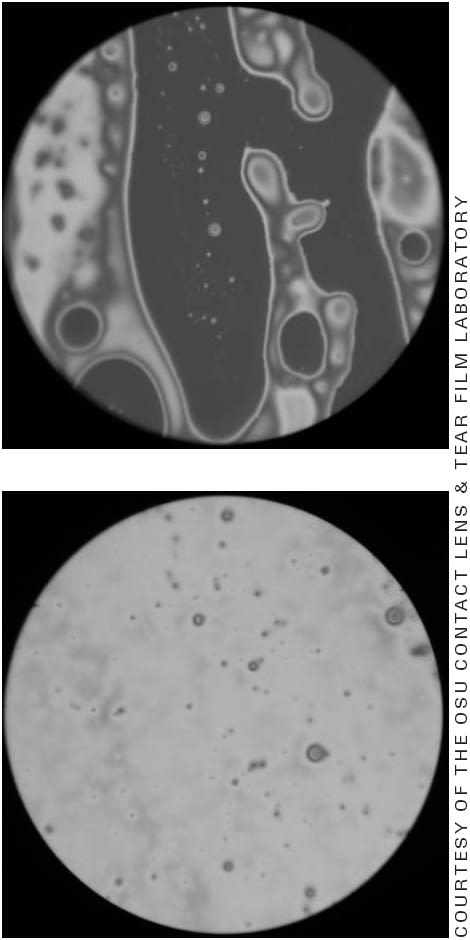

An obstructive form of MGD is associated with skin disease. It is characterized by abnormal or hyperkeratinization of the meibomian gland ducts and is a probable precursor to inflammation (Bron, 2004; Driver, 1996). Obstruction of the duct leads to reduced meibum in the tear film, resulting in dry eye from increased tear evaporation. Figure 3 shows images of the tear film lipid layer using a microscopy procedure. In addition, lipid production is reduced in the gland itself as a likely result of meibomian gland atrophy. Figure 4 shows the appearance through meibography of both partial and entire meibomian gland loss in patients who have MGD.

Figure 3. Tear film lipid layer microscopy. The top image represents a thinned lipid layer (as noted by the darkened areas) in a patient who has severe MGD. The average lipid thickness in this photo was 14nm. The bottom image represents the appearance of a normal lipid layer with an average thickness of 69nm.